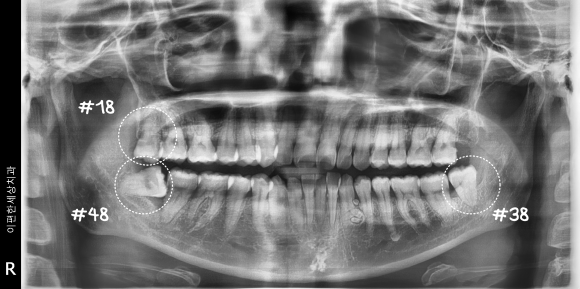

촬영일 : 240610

처음 오셨을 때 촬영한 사진입니다.

사진을 보면 위쪽 사랑니 1개, 아래쪽 사랑니 2개

총 3개가 자라 있는 것을 확인할 수 있는데요.